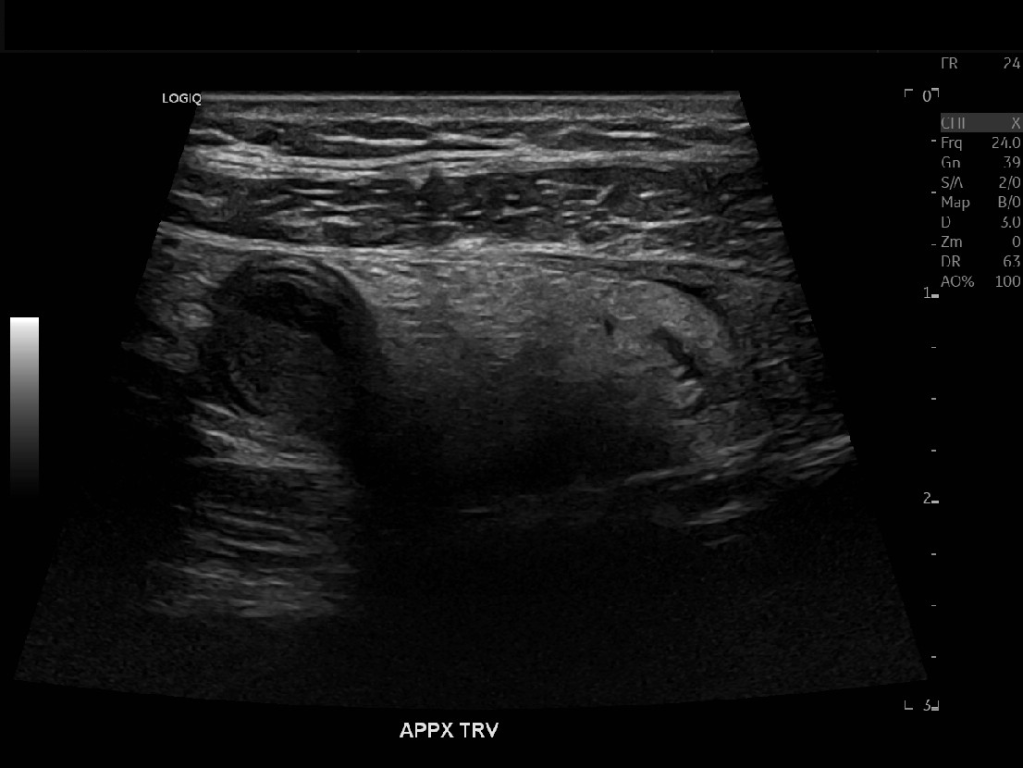

Appendicitis 13

Acute appendicitis @ 1 cm with L2-9mhz and L6-24mhz transducer GE Logiq e10.